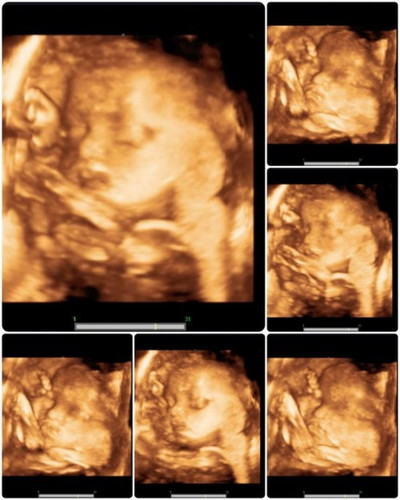

อ่านเพิ่มเติมท้องแรก ค่ะ ลูกสาว กำหนด 15/1/66 ไปซาวด์ล่าสุดตอน 29+6w นน.น้อง 1813 กรัม แม่เพิ่มมา 8 กิโล ตรวจน้ำตาลผ่านฉลุยค่ะ อาทิตย์หน้าคุณหมอนัดที่ 33+2w ลุ้นว่าแม่จะขึ้นกี่โล ลูกขึ้นอีกเท่าไหร่จ้า อาการแม่ตอนนี้ ปวดขาหนีบบ้างบางวัน แต่อึดอัดทุกวัน 😍😍